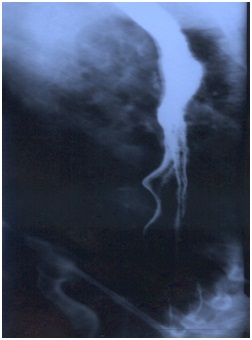

Endoscopy revealed changes of 'Beak-like narrowing' of the lower end of the esophagus and reduction in the motility of the Esophagus, which is diagnostic of Achalasia Cardia. The stomach and duodenum were normal.

Before the treatment

Beak-like narrowing oesophageus because of stricture